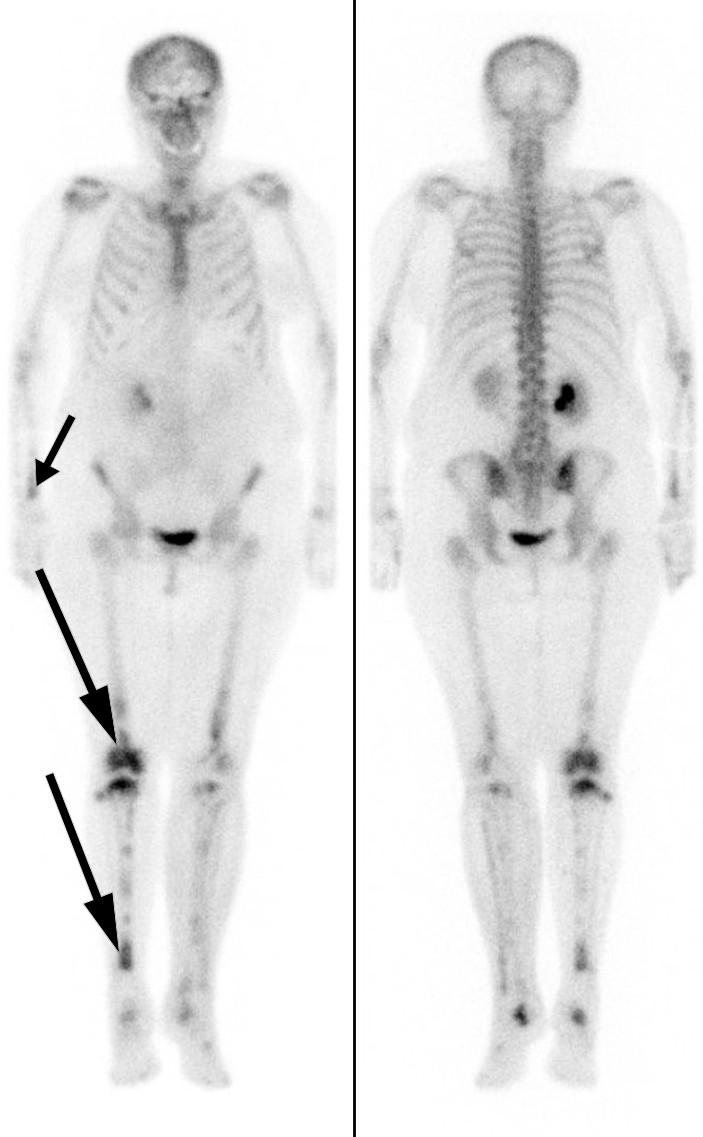

I tillegg til de perinefriske forandringene var det påfallende funn på CT thorax (fig 2) og helkroppsscintigrafi (fig 3). Som et bifunn ble det også funnet en liten lungeembolus. MR hjerte og ekkokardiografi påviste lokalt fortykket perikard, mens MR caput og orbita viste normale funn. Abdominal paracentese viste CD68-positive og CD1a-negative makrofager og ingen tegn til mikrober. I ascitesvæsken, som var gjennomskinnelig og gul, var albuminnivået 13 g/l og proteinkonsentrasjonen 24 g/l (under 30 g/l tydet på transudat). Serum-ascites-albumin-gradienten (SAAG) var 9 g/l, forenlig med at årsaken til ascites ikke var portal hypertensjon. Leukocytter i ascitesvæsken var 0,20 · 109/l, noe som utelukket spontan bakteriell peritonitt. På blodutstryk var det granulocytose og trombocytose, mens benmargsutstryk viste reaktiv/normal benmarg. Benmargsbiopsi viste noen svakt reaktive megakaryocytter, og biopsier fra femur påviste kun osteomyelosklerose. Biopsi fra perinefrisk vev viste fibrose og histiocytter som var positive for CD68 og negative for CD1a, samt en uspesifikk reaksjon for S100-proteiner. Genetisk testing for BRAF-mutasjon var negativ.

Flere differensialdiagnoser ble diskutert. Allerede da tilfellet ble drøftet med universitetssykehus første gang, ble det fra radiolog, grunnet hårete nyrer, påpekt muligheten for Erdheim-Chesters sykdom (ECD). Basert på kliniske funn, blodprøver, radiologi og histologi pekte dette seg ut som den mest sannsynlige diagnosen. Det ble startet behandling med interferon-α, men behandlingen hadde ingen effekt på sykdomsaktivitet, og pasienten utviklet bivirkninger i form av influensalignende sykdom. Hun ble innlagt på et annet universitetssykehus, hvor det ble satt i gang kombinasjonsbehandling med mTOR-hemmeren sirolimus og prednisolon. Allerede etter få dager var det klinisk bedring, og fire måneder senere var hun betraktelig bedre. Feberen og hosten gikk tilbake, mens SR, leukocytter, hemoglobin og albumin var normalisert. På dette tidspunktet var det også foretatt PET-CT som viste regresjon av de patologiske funnene. Pasienten følges nå med jevnlige kontroller.

Diagnosen Erdheim-Chesters sykdom er basert på kliniske, radiologiske og histologiske funn. Det vanligste er affeksjon av skjelettet, sentralnervesystemet, nyrene og det kardiovaskulære systemet (24, 25). Infiltrasjon i orbita er også beskrevet, for eksempel i en kasuistikk i Tidsskriftet fra 2014 (26). Symptomene avhenger av organaffeksjon, men det typiske er skjelett- eller leddsmerter, dyspné, hoste, eksoftalmus eller xantomer samt synsforstyrrelser, ataksi, hodepine eller andre nevrologiske symptomer. Kardial affeksjon er ofte asymptomatisk, men det kan ha store konsekvenser. Perikardsykdom som perikarditt, perikardvæske eller tamponade rammer opp mot 45 % av pasientene. Det er mer uvanlig med histiocyttinfiltrasjon i myokard og koronarkar, som kan føre til iskemi, klaffefeil eller ledningsforstyrrelser (27). Vår pasient hadde fortykket perikard, visualisert både på CT thorax, MR hjerte og ekkokardiografi, men ingen perikardvæske og god hjertefunksjon for øvrig.

Symmetrisk osteosklerose i diafysene og metafysene i lange rørknokler, inflammatoriske forandringer rundt aorta (coated aorta) og perirenal infiltrasjon av histiocytter (hårete nyrer) er typiske radiologiske funn (25, 28, 29). Sistnevnte er nærmest patognomonisk for tilstanden og en viktig grunn til at diagnosen tidlig ble mistenkt hos vår pasient. Det histologiske bildet er karakterisert av lipidfylte såkalte skumhistiocytter, ofte kombinert med fibrose. Immunhistokjemisk vil de være positive for CD68, CD163 og faktor XIIIa, og i noen tilfeller for S100, som skiller dem fra histiocytter ved en del andre tilstander. De vil også være negative for CD1a og langerin (CD207) (27).